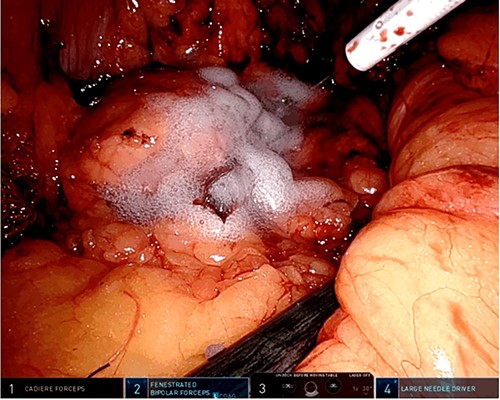

A robotic redo distal pancreatectomy was performed. Adhesions from the previous operation were taken down and the pancreatic stump was dissected. Samples of lymphatic tissue were sent for permanent pathology. An intraoperative ultrasound scan was done to localize the tumor and rule out concomitant lesions. A 2-cm nodule was found in the pancreatic stump (Fig. 3). With precise dissection, the gland was mobilized, reaching the confluence of the splenic and the portal vein. Afterward, the pancreatic stump was resected using a linear stapler (Fig. 4A and B). Once hemostasis was obtained, fibrin glue was applied to the section line and two drains were left close to the stump (Fig. 5). The patient was discharged on postoperative day 7. She developed a pancreatic biochemical leak that was managed conservatively. The histopathology analysis showed a grade 2, 1.3 cm well-differentiated neuroendocrine tumor with a low mitotic rate and Ki 67 index of 3%. After 16 months of follow-up, there was no evidence of recurrence.